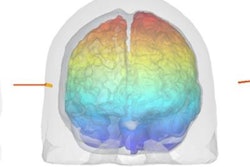

Unfortunately, there are obstacles to overcome. For example, cancers evolve in time to become harder targets to treat. So how can medical physics help? "We need to capture the whole disease and the evolution of disease, using multimodality imaging techniques such as optical and molecular imaging," Jeraj explained. In radiation therapy, such a shift from anatomical imaging and population-based treatment, to molecular imaging, patient-specific therapies and nonuniform dose delivery is the foundation of "biologically conformal radiotherapy."

Looking forward, Parodi suggests that we may now be entering the era of biological guidance. "The next dimension to explore for ART is biological guidance," she told the delegates. One example is the use of PET for stratification, therapy personalization, and response assessment. Including oxygen-enhancement ratio in ion beam planning, meanwhile, could enable dose or cell killing painting of inhomogeneous tumors.

Parodi concluded by presenting some emerging methods that exploit biology. These include micro- and minibeam therapies, spatially fractionated approaches designed to spare healthy tissue that have been demonstrated with both photon and proton beams. Another possibility is to use nanoparticles for tumor vascular disruption during radiotherapy.